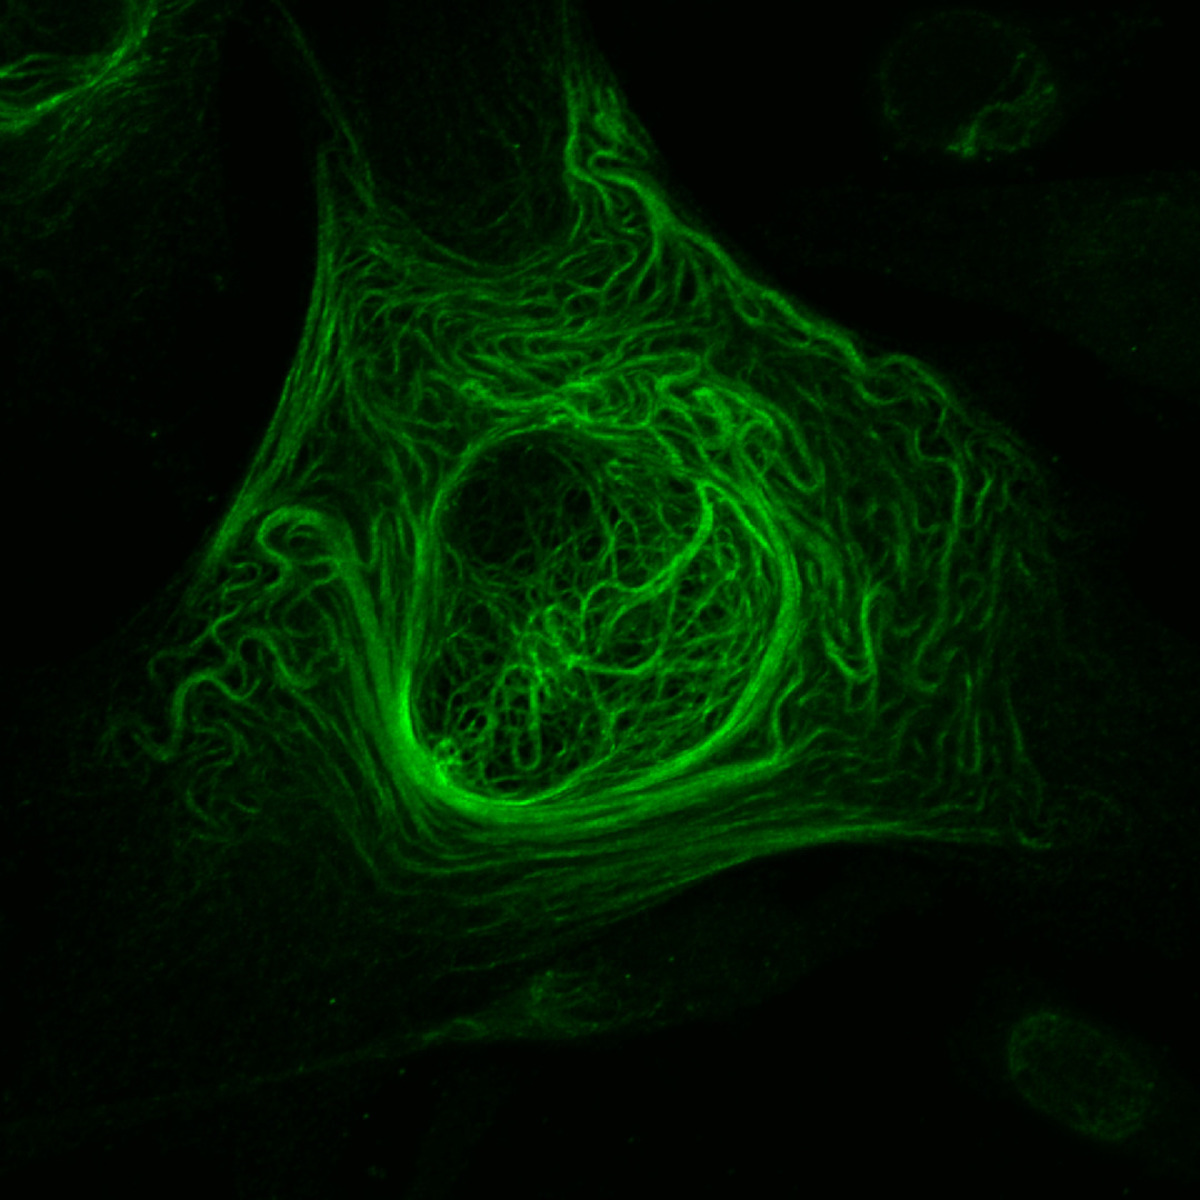

1. Συσταλτά μυοεπιθηλιακά κύτταρα

Η φωτογραφία αυτή κέρδισε το δεύτερο βραβείο του διαγωνισμού! Ανήκει στον επιστήμονα Caleb Dawson και δείχνει συσταλτά μυοεπιθηλιακά κύτταρα τυλιγμένα γύρω από κυψελίδες παραγωγής γάλακτος.